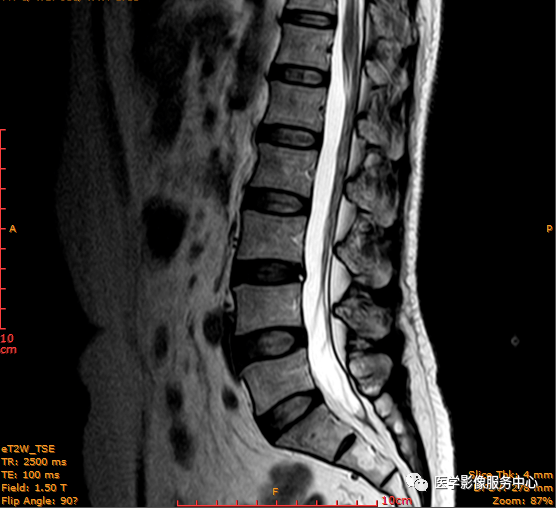

患者 女性 54岁 因腰背部疼痛不适数月,下腰时疼痛明显而入院;

病史:患者3个月前开始出现左侧腰背部酸痛不适,当时未重视,后腰背部疼痛加重,偶伴左下肢麻木伴小腿放射性疼痛,经休息有所好转,久坐后症状明显加重;

查体:L3-4、L4-5棘突处压痛(+),四肢肌力、肌张力正常,触痛觉正常,双侧膝腱反射正常,双侧跟腱反射正常,双侧巴彬斯基(-)。

临床诊断 :腰突症?故行腰椎MRI检查,图像如下:

T2矢状位

这个患者腰椎间盘膨出程度不明显,神经根没有明显的受压,椎管未见明显狭窄,那这个患者腰疼的“罪魁祸首”是腰椎间盘膨出嘛?

大家有没有留意到还有哪个地方不正常呢?

L3-4椎间盘后缘可见点状高信号区(红色箭头所指处)

红色箭头所指的异常信号区是是什么呢?平时工作中大家有没有遇到这种情况,你会不会忽略这个异常信号?有没有想过这个椎间盘后缘高信号区是引起患者腰疼的重要因素呢?下面为大家重点介绍。